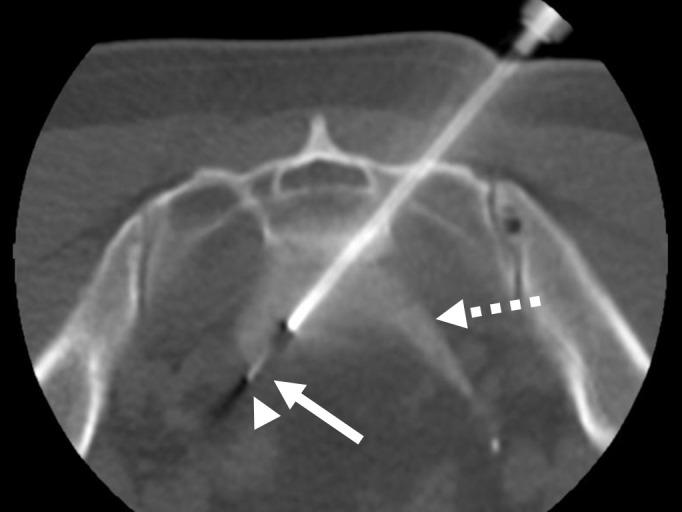

A 60-year-old man with a history of prostatic adenocarcinoma in a plan for resection of hypogastric adenopathy. Image guided pre-surgical marking was indicated.

Preoperative marking was performed with local anesthesia under computed tomography with transosseous access and hydrodissection.

在计算机断层扫描引导下,采用经骨穿刺和水分离技术,在局部麻醉下进行了术前标记。